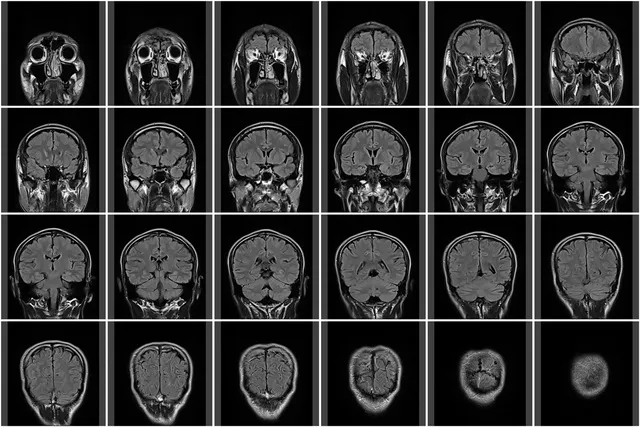

大きく分けると、頭痛は「一次性頭痛」と「二次性頭痛」の2つの種類に分類されます。

② 二次性頭痛(にじせいずつう)

これが要注意!

脳の病気(くも膜下出血、脳腫瘍、髄膜炎など)や、他の体の病気(高血圧や副鼻腔炎など)が原因となって起こる頭痛です。

中には、命に直結する危険な頭痛が含まれています。

二次性頭痛とは、前述の通り、脳の病気(くも膜下出血、脳梗塞、脳出血、脳腫瘍、髄膜炎など)が原因で起こる頭痛です。